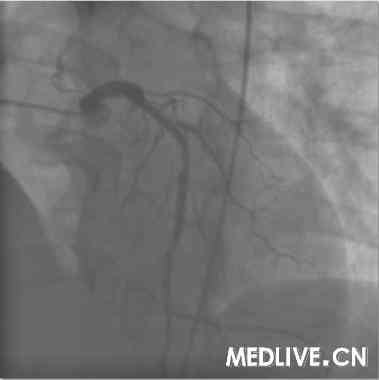

术前血管造影(附图):

冠造结果(图2-4):回旋支中段100%闭塞;右冠中段100%,并见大量血栓影;前降支中段不规则狭窄50%。结合临床,考虑右冠为急性心肌梗死相关冠脉,应首先对其进行急诊介入治疗。